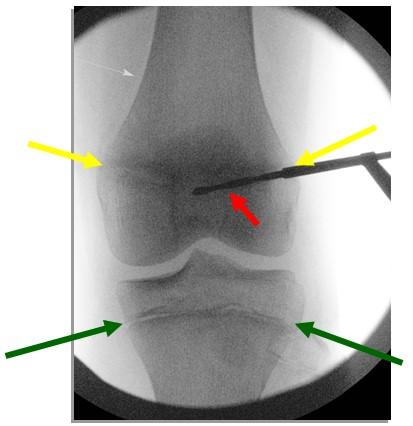

Tijdens de operatie wordt met behulp van een röntgenapparaat bepaald waar de groeischijf zich bevindt welke zal worden beschadigd. Er wordt een litteken gemaakt aan weerszijden van deze groeischijf en met behulp van een boor wordt de groeischijf dermate beschadigd dat deze na de operatie niet meer zal groeien. De littekens worden gesloten met behulp van oplosbare hechtingen. De littekens zijn ongeveer 1 a 2 cm groot. De operatie duurt per groeischijf 10 a 15 minuten. Om het geopereerde been wordt een drukverband aangelegd.

Figuur 1: Röntgen opname van een knie tijdens de operatie. De rode pijl wijst naar de boor. Tussen de gele pijlen loopt de groeischijf net boven de knie, tussen de groene pijlen de groeischijf net onder de knie.